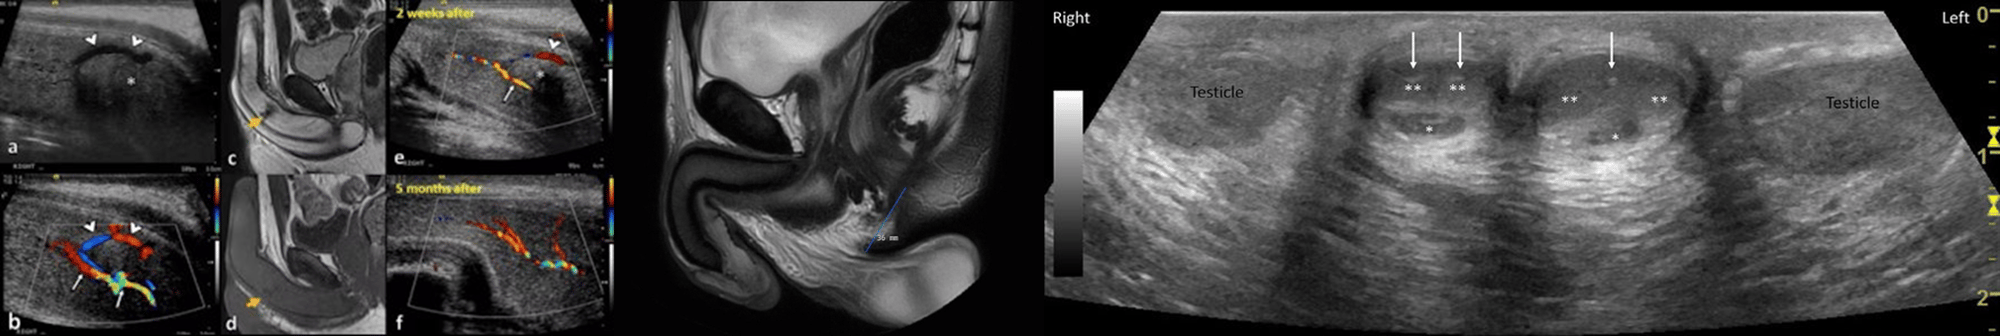

The session will cover the latest advances in multiparametric scrotal ultrasound, penile ultrasound, and penile MRI, offering practical insights and imaging techniques to enhance diagnostic accuracy. This day will be of interest to any trainees wishing to further their knowledge of penile-scrotal imaging!